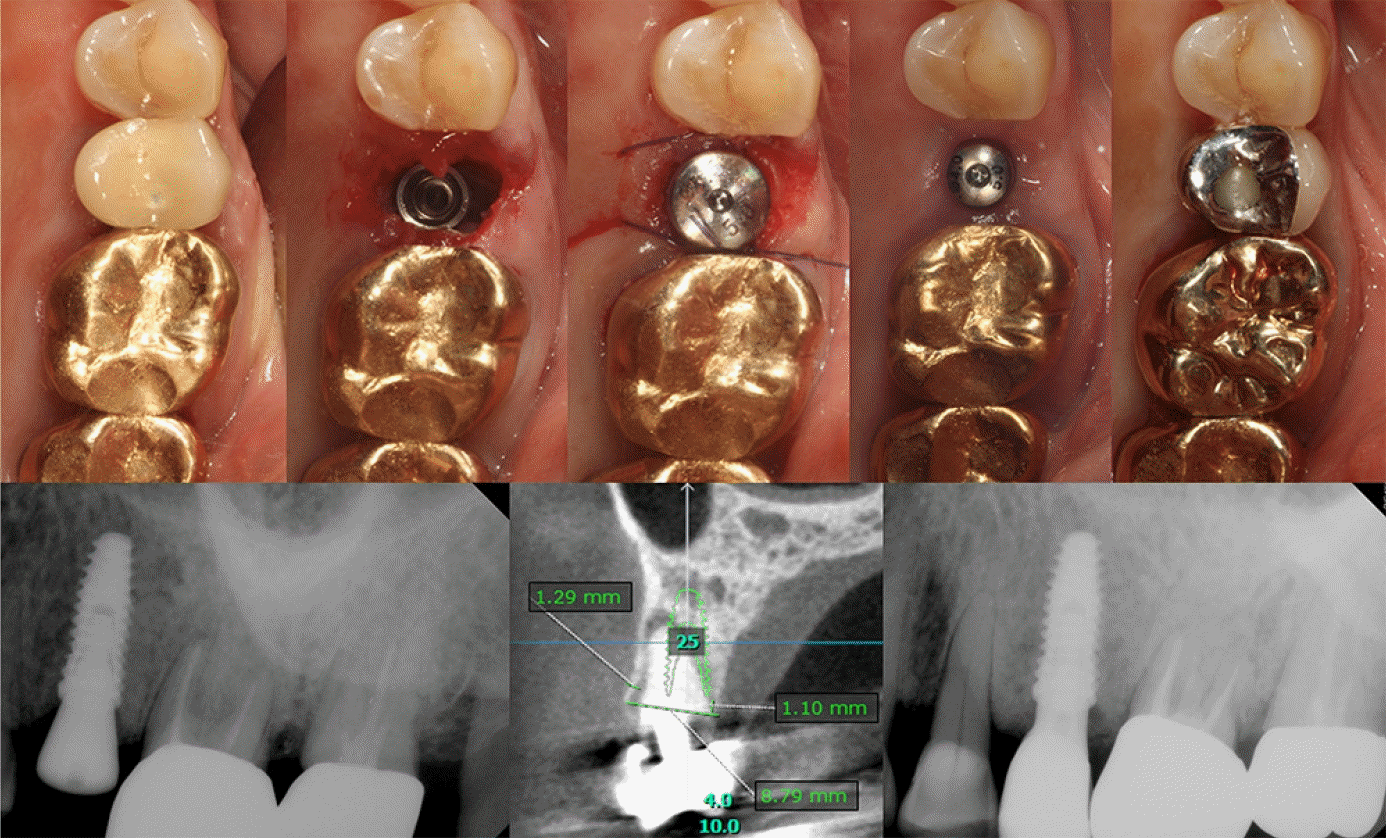

Case 2: Immediate implantation of #25i

A 75-year-old female patient who was referred from the Department of Conservative Dentistry visited to extract the maxillary left second premolar which had a history of root canal treatment and crown restoration about 15 years ago at a local dental clinic. A periapical radiolucency and poorly positioned post in a calcified canal were found on the radiograph and the tooth was judged hopeless. A virtual planning using the pre-operative CBCT(OnDemand3D version 1.0, Cybermed Inc.) revealed that both the buccal and palatal walls were intact in the cross-sectional view. A 4.0 x 11.5-mm, SLA-surfaced implant(IS-III Active, Neobiotech, Seoul, South Korea) was placed immediately after extraction and porcine-derived bone graft(THE Graft, Purgo Biologics) was applied in the buccal gap defect, which was covered by a collagen sponge(CollaTape, Zimmer Biomet, Warsaw, USA) and HA(Healing abutment, Neobiotech), followed by suturing with a resorbable 4-0 glyconate monofilament suture material (Monosyn®, B. Braun)(Figure 2).

Figure 2.

Clinical photographs and radiographs of Case 2 with HA connection after immediate implantation.